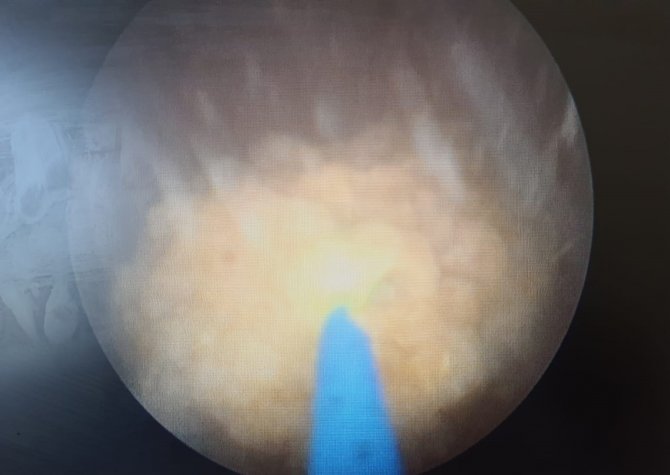

Ameliyat öncesi hazırlıkların tamamlanmasıyla anabilim dalından Dr. Alpaslan Yüksel tarafından operasyona alınan hastanın 22 mm'lik taşı, endoskopik lazer tedavisiyle kırıldı. Operasyon sonrası sağlığına kavuşan hasta, işlemin ardından ertesi gün taburcu edildi. 10 gün sonra kontrole gelen hasta, tüm şikayetlerinin kaybolduğunu ve iştahının açıldığını belirtti.